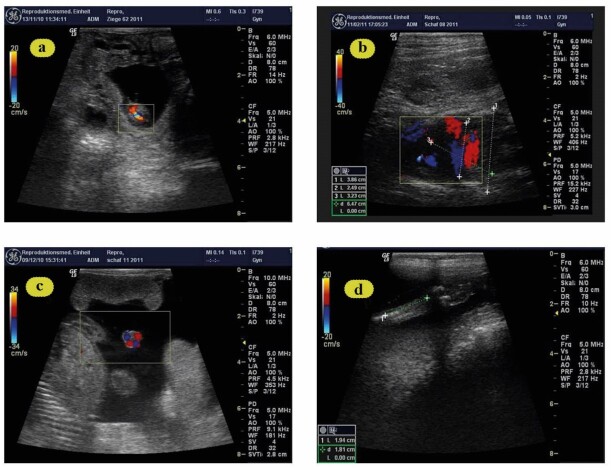

This study aimed to examine the efficacy of Doppler and B-mode sonography in evaluating the impact of maternal temperament on hemodynamic alterations in both the fetus and uterus during ovine gestation in addition to alteration of the angiogenic protein expression and fetal biometry. Twenty Ossimi ewes were divided into two groups, more reactive (MR: 12 sheep) and less reactive (LR: 8 sheep). Several endpoints were assessed every 2 weeks (wk) from breeding to wk 20 of pregnancy. Blood samples were taken to evaluate the expression of angiogenic proteins at parturition. The resistance (RI) and pulsatility (PI) indexes of the uterine (UtA) and fetal umbilical arteries (UMA) were measured. Biometry includes: diameter of amniotic vesicles (AVD), umbilicus (UMD), fetal thoracic diameter (FTD) and metacarpal length (MCL). The UtA-PI was higher in MR compared to LR ewes between 6-12 wks of gestation (P>0.01), while a tendency was recognized at wk 14 (P=0.054). The same was true for UtA-RI during the first 8 wk of pregnancy (P < 0.03) when MR and LR animals were compared. Similarly, UMA-RI was higher in fetuses of MR than LR ewes at wk 14 (P<0.0003) and 20 (P<0.02) of pregnancy. The differences in UMA-PI reached significance at wk 6, 8, 10, and 20 (P<0.0 -0.003). Furthermore, significant changes in fetal biometry were investigated. The expressions of VEGF, NOS3 and HIF 1α were increased in the less reactive sheep (P<0.001). In conclusion, the maternal temperaments affect the Doppler, B mode as well as the expressions of mRNAs for VEGF, NOS3 and HIF 1α genes at time of parturition.